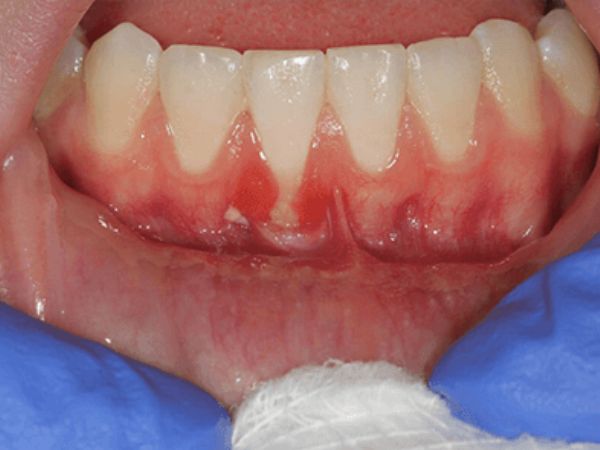

Before